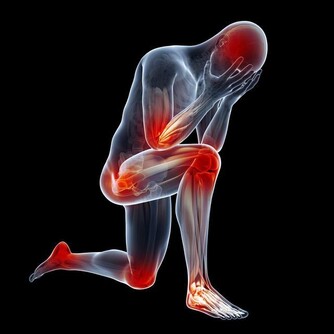

最後運動要因人而異,切不可不服老。年輕人陽氣旺盛,稍多些運動挺好;中老年人陽氣已虛,運動量要低於年輕人。根據個人身體狀況控制好運動量,對於膝蓋受損的人群,千萬不可迷信“每日堅持1萬步”的運動雞湯。

功效:具有舒筋活絡、益氣活血、解除肌肉疼痛等功效,適用於熬夜後肌肉酸痛、頸部脹痛熬夜者食用。